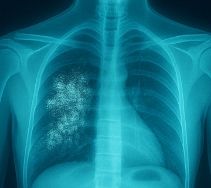

폐결핵 증상 vs 기타 결핵 유형

결핵 증상이 의심된다면 보건소나 병원을 통해 객담 검사, X-ray 등 정밀 진단을 받는 것이 필수입니다.